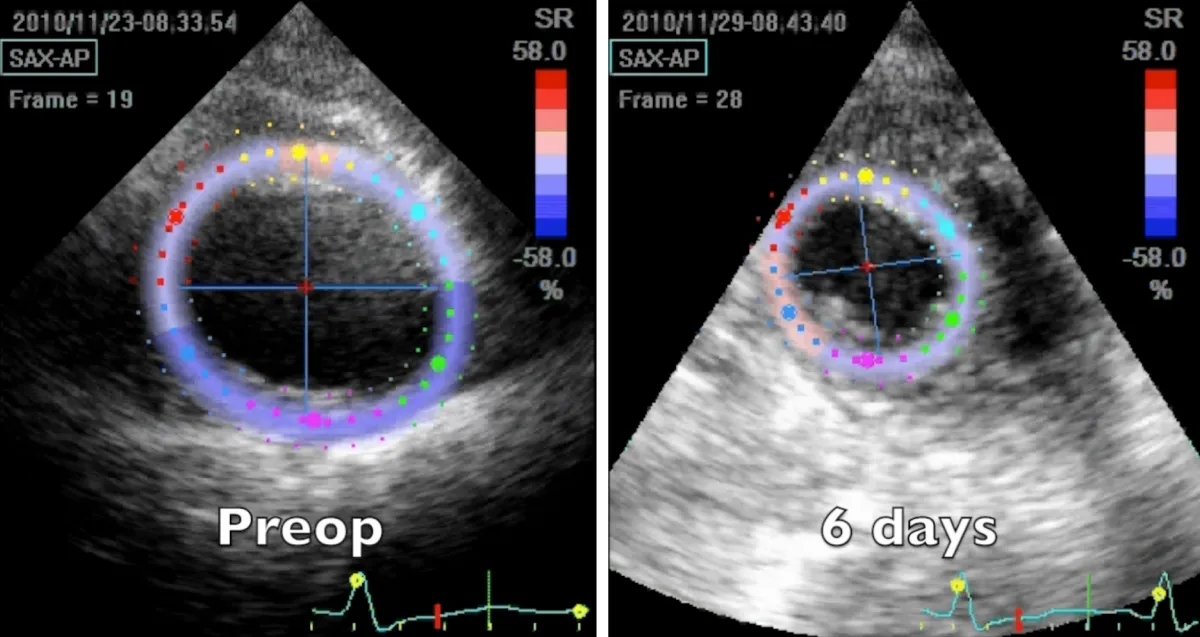

Apical region study (Figure 4 and Video 5) clearly demonstrates an improvement in apical geometry and rotation (from - 4.1 degrees to 4.6 degrees) in the immediate postoperative period induced by the surgically reoriented bundles of fibers. Consequently, left ventricular torsion improved to 7 degrees after the operation, with a reduction to about 4 degrees four years after surgery, due to a new-onset small apical dyskinetic area that reduces counterclockwise rotation to 1.3 degrees. Magnetic resonance short axis views (Figure 3 and Video 4) highlight the physiologically restored left ventricle along its whole length, from the apex to the base. The key surgical steps of this technique are: a) the septal rim of the suture is as long as the patch; b) the lateral rim of the suture shrinks the displaced fibers to a more physiologic orientation, given that it must adapt the dilated lateral wall onto the patch; c) a new apex is rebuilt (elliptic shape); d) a very small “akinetic” patch is used to bring closer the normal myocardium, redirecting fibers in a more physiologic disposition (Video 6).

Figure 4: 2D speckle tracking echocardiography short axis apical systolic frames at two controls, preoperative and 6 days after the operation.

Video 5: Echocardiography apical short axis view; comparison between preoperative and 6 days after the operation controls. Note the abnormal clockwise rotation of the preoperative dilated apex and its near normal functional counter clockwise rotation few days after the surgical correction.